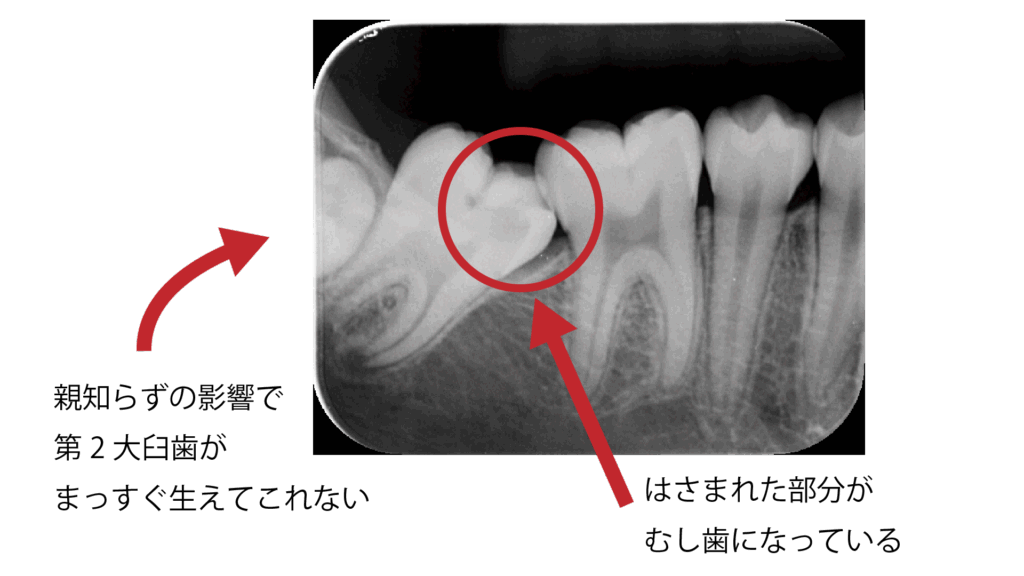

永久歯が生えてくる際、隣の歯に引っかかってまっすぐ生えてこないことがあります。これを萌出障害(ほうしゅつしょうがい)と言います。

引っかかったまま放置すると、その部分にむし歯ができやすくなります。一度むし歯になると進行が早く、治療も難しくなるため、部分矯正で早めに角度を修正することが大切です。